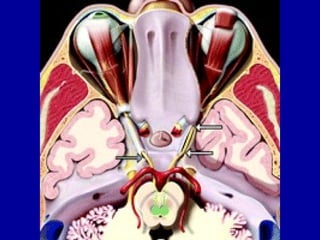

Orbital segment

• The oculomotor nerve enters the orbit through

the superior orbital fissure within the annular

ring or Zinn.

• It divides into superior and inferior divisions.

• The superior division supplies the contralateral

superior rectus & levator palpebrae superioris

muscles bilaterally.

• The inferior divison supply the ipsilateral inferior

& medial recti & inferior oblique muscles.